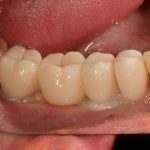

Рекомендации по установке имплантов. Для всех. Часть V.